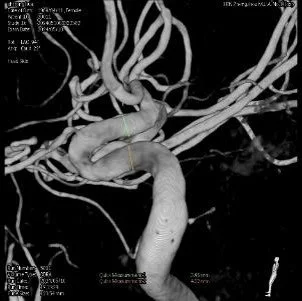

Tubridge Plus Case 5